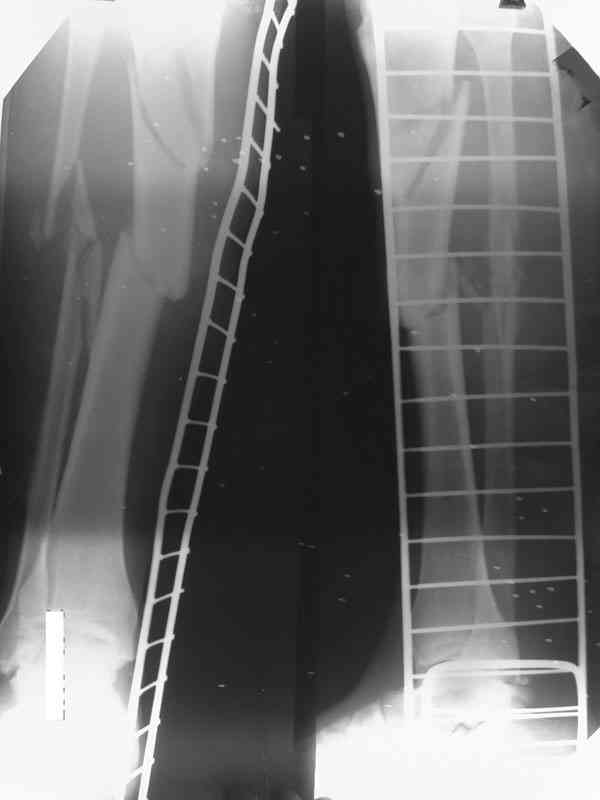

[Ortho] Дефект и остеомиелит tibia

Хотелось бы уточнить позицию по д-зу на данный момент-Хронических заболеваний у пациента нет.  Свищ по передней поверхности в проксимальном отделе дистального фрагмента до 3 мм. Выделения серозно- геморагического характера. Явных признаков воспааления м/т нет и не было на протяжении 4 мес.

Доводим также к сведенью что дистальный межберцевый синастоз уже состоялся, ложный сустав малоберцевой кости в с/з. Учитывая так же отсутстаие нормального обеспечения больного в послеоперационном периоде мы склоняемся к аппарату внешней фиксации.

Как дополнение высылаю снимки и фото конечности, чтобы Вы могли оценить состояние м/т, и течение заболевания.